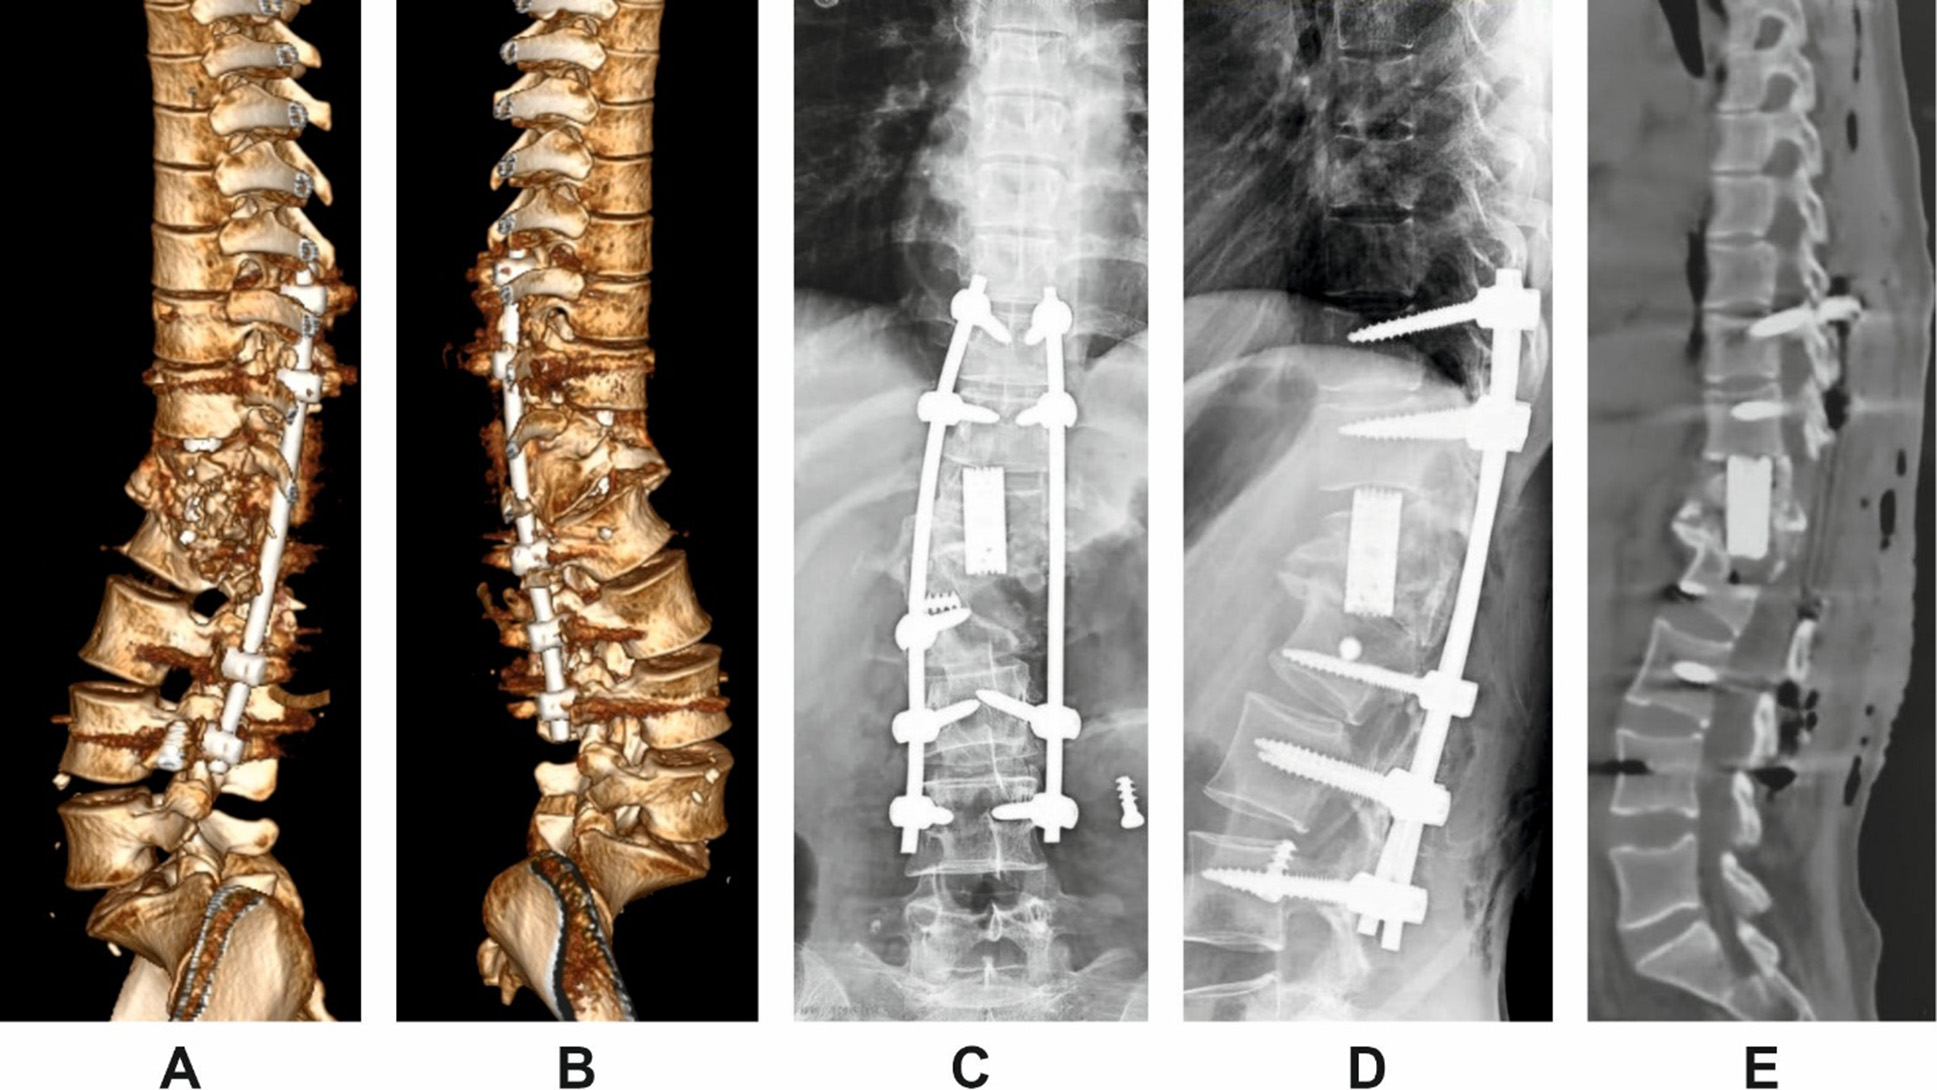

The patient underwent revision surgery via a posterior-only approach. The procedure involved posterior instrumentation with pedicle screws, vertebral body resection, cage placement, and posterior column osteotomy for correction of the deformity. Anterior implants were not revised. Postoperative imaging confirmed restoration of sagittal alignment and segmental stability (Fig. 3).

Fig. 3. Postoperative imaging following posterior revision in Patient H.

A and B: 3D lateral reconstructions from left and right sides;

C and D: scout views (anteroposterior and lateral);

E: midsagittal CT reconstruction demonstrating correction of segmental alignment.